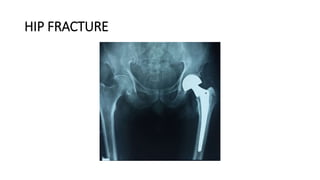

HIP FRACTURE

DEFINITION

• is a break in the upper quarter of the femur (thigh) bone. The extent

of the break depends on the forces that are involved. The type of

surgery used to treat a hip fracture is primarily based on the bones

and soft tissues affected or on the level of the fracture.

CAUSES

• Hip fractures most commonly occur from a fall or from a direct blow

to the side of the hip.

• Some medical conditions such as osteoporosis, cancer, or stress

injuries can weaken the bone and make the hip more susceptible to

breaking. In severe cases, it is possible for the hip to break with the

patient merely standing on the leg and twisting.